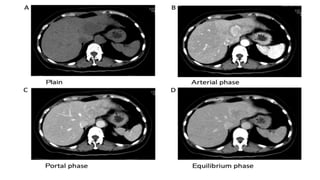

Hypovascular Metastasis

• Colon, lung, prostate, gastric, and bladder carcinomas

• PVP as hypoenhanced masses relative to the adjacent liver and can also show delayed

enhancement

Hypervascular metastasis:

• NE tumor, RCC, melanoma(ocular), sarcoma, and thyroid ca

• U/S ->hypoechoic halo, central calcification

Wash out

• T2 hyperintense on MR imaging